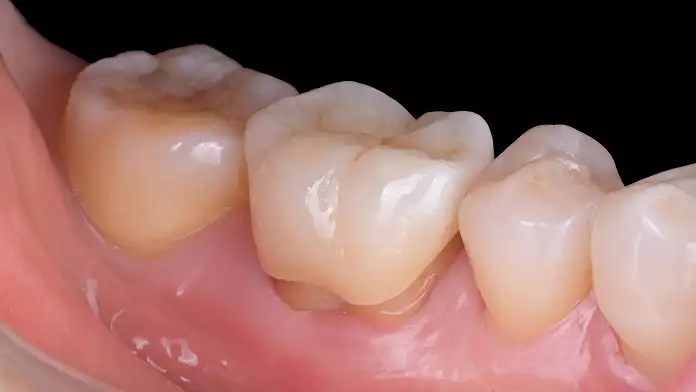

힘을 많이 받는 치아의 뾰족한 부위(교두)가 손상되었거나, 균열(Crack)이 있어 파절 위험이 높은 경우 시행합니다. 크라운처럼 전체를 깎지 않고도 약해진 치아 윗부분을 보강하여, 치아가 쪼개지는 것을 예방하는 핵심적인 보존 술식입니다.

크라운에 비해 치아 삭제량을 극적으로 줄여주면서, 치아의 핵심 구조를 보존하는 고난도 보철 술식입니다. 치아의 수명을 연장하기 위한 생체 모방적(biomimetics) 접근법입니다.